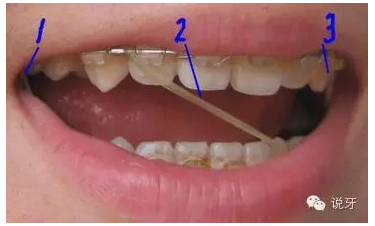

9、上橡皮筋

一般來說,牙齒的排齊會(huì)因本身的牙齒移動(dòng)快慢和醫(yī)生的技術(shù)各方面因素而不同。一般1個(gè)月左右能顯現(xiàn)出一些變化,而6個(gè)月左右基本排齊。牙齒排齊以后牙縫開始收合,此時(shí)需要皮筋的幫忙。需要注意的是皮筋在吃飯時(shí)需要摘下來。

QQ圖片20150730111128.png